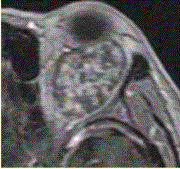

患者女,30岁,左眼球突出,运动障碍7个月。MRI平扫示左肌锥内等T信号影(下图)。增强扫描示均匀增强,眼肌、眼环正常。下述眼眶病变中,属于肌...

问题 患者女,30岁,左眼球突出,运动障碍7个月。MRI平扫示左肌锥内等T信号影(下图)。增强扫描示均匀增强,眼肌、眼环正常。 下述眼眶病变中,属于肌锥外病变的是